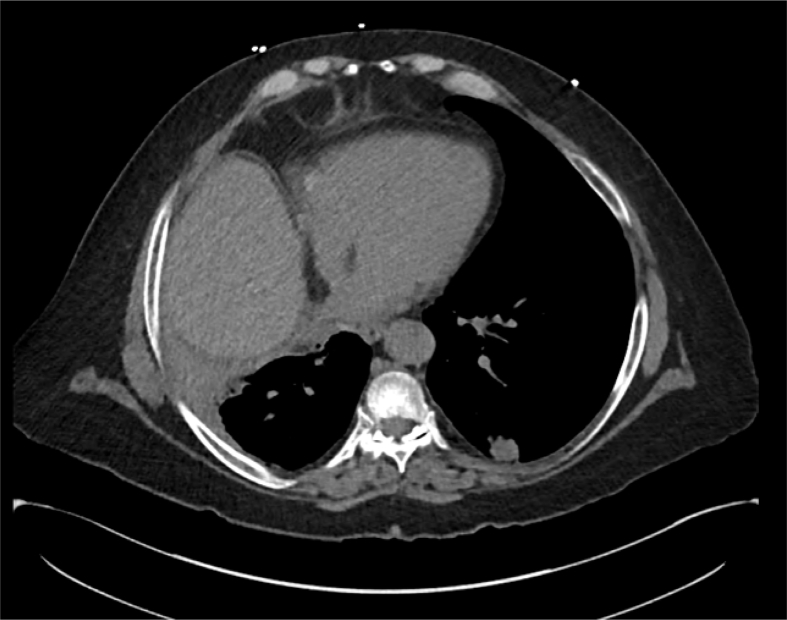

Fig. 3.

Resolution of intracardiac free air.

The patient was admitted to the medical ICU where management via hyperbaric oxygen was considered. This therapy, however, was deemed unsuitable given the presence of the post-procedural pneumothorax. Instead, she was treated with a conservative approach which included positioning in a right lateral decubitus and Trendelenburg position to reduce the risk of embolization into the systemic vasculature. She was also administered 100% oxygen via a nonrebreather mask on which she remained for approximately 24 hours. A repeat chest CT the following day revealed complete resolution of her intracardiac free air, and MRI brain concurrently performed demonstrated no residual abnormalities from presumed transient ischemic attack related to microscopic air emboli. She was monitored without further intervention before being discharge home the next day.